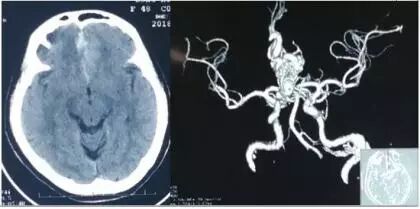

11月上旬,48歲的張女士突發頭痛,持續5小時,家人緊急把她送往附近醫院,頭部CT提示蛛網膜下腔出血,CTA提示動靜脈畸形,因病情嚴重,張女士被緊急轉送到市立醫院神經外二科。

左頸內動脈正側位各時象,左側頸內動脈造影提示左額畸形血管團。

在持續進行兩個多小時手術後,兩個動脈瘤均被順利成功夾閉。術畢,又再行腦血管DSA復查,結果顯示動脈瘤均夾閉完全,正常血管保留完好,血流通暢。術後造影,血管團消失。隨後又進行了術中頭顱CT,未見明顯出血或低信號灶。

▲術後造影,血管團消失。